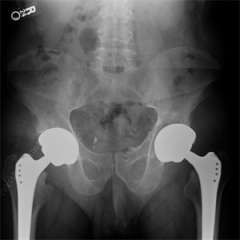

xray showing hips that have undergone joint replacement.

UCLA Joint Replacement Service surgeons are experts in the spectrum of joint replacement procedures for the hip and knee. Surgical treatment often involves a total joint reconstruction/joint arthroplasty. For the knee this may involve unicompartmental knee replacement or total knee replacement. A small subset of patients may be candidates for a bone realignment procedure called an osteotomy. For the hip, treatment may involve a bone-conserving surface replacement procedure or a total hip replacement. A total hip replacement replaces your damaged hip joint with an artificial one. The surgical procedure can be performed from behind the hip, to the side of the hip, or from the front of the hip. We have experts who perform the Anterior Hip Replacement surgery. Again, a small subset of patients may be candidates for osteotomy procedures.